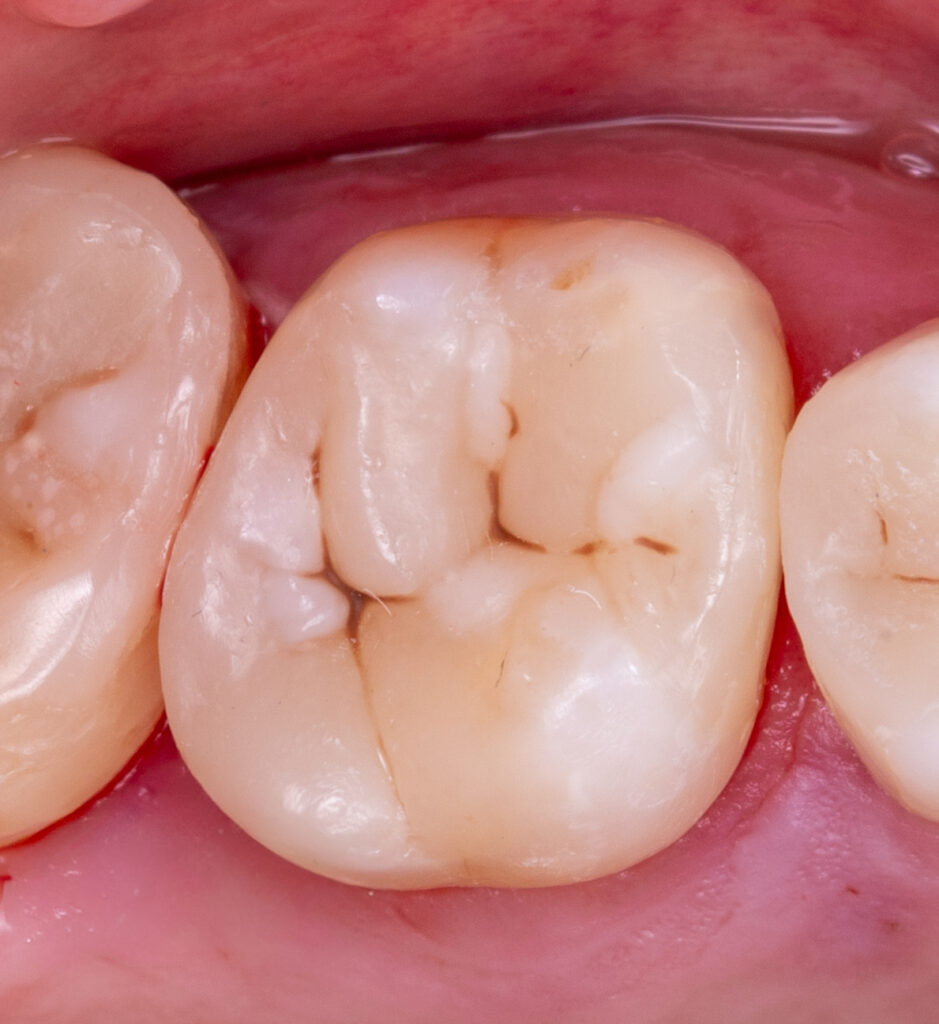

Wooden wedges and a Palodent matrix system were applied to ensure proper embrasure and facilitate proximal wall restoration. The proximal walls were rebuilt using Asteria A2B composite, and EverX Bulk Fill was placed inside the tooth to reduce stress, minimizing the C-factor and polymerization stress. The tooth anatomy was subsequently restored with NeoSpectra in shades A2 and D1, and the fissures were stained with Mecherium Color Brown.